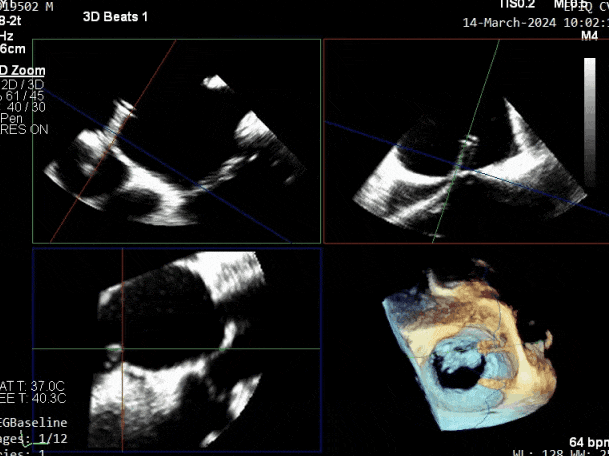

超声心动图:

二尖瓣后叶活动受限,呈房源性栓系,以P3区为重,二尖瓣前叶假性脱垂,二尖瓣瓣环前后径49mm,左右径40mm。

PISA法测r=12mm,EROA=0.72cm2,RVOL=100ml,RF 26%。LVEDD 57mm,左房71*59*77mm,右房55*69mm,LVEF 70%。

超声提示:

二尖瓣反流(重度,4+级,Carpentier I型)

三尖瓣反流(轻度)

主动脉瓣反流(轻度)

双房及心耳内未见确切血栓回声